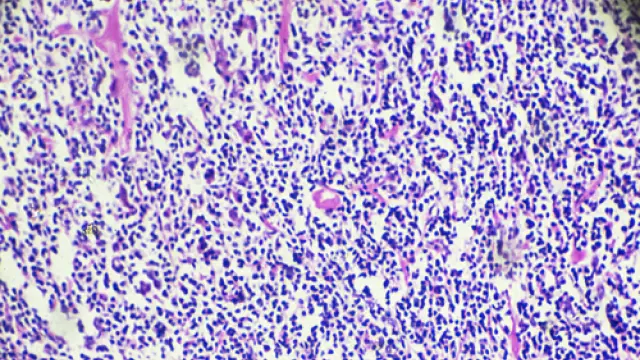

Los linfomas son cánceres que comienzan en los glóbulos blancos llamados linfocitos. Existen dos tipos principales de linfoma: Linfoma de Hodgkin (HL) y Linfoma no Hodgkin (NHL). Los dos tipos de linfoma se comportan, se propagan y responden al tratamiento de manera diferente.

Cuando las células afectadas son los linfocitos (que son un subtipo de glóbulos blancos muy importantes que forman parte de nuestras “defensas”), y se originan en el sistema linfoide (ganglios linfáticos, bazo, …), hablamos de un diagnóstico de linfoma.

El linfoma de Hodgkin se empieza a producir cuando los mecanismos de control de los linfocitos se alteran, se inicia una división celular alterada e incontrolada.